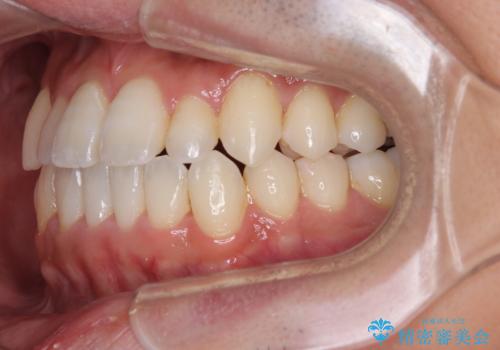

内側に引っ込んだ歯を治したい インビザラインの矯正治療

- 前歯のデコボコとクロスバイトを治したいとのことで来院された患者様です。

上下顎ともに歯列全体の側方拡大とIPR(歯と歯の間を削る)によってデコボコとクロスバイトが解消するように設計し、インビザラインにより治療を行うこととしました。

反対咬合特有の治療途中の前歯の干渉が長く続き、治療中に食事をとりにくく、ご迷惑をおかけしました。

前歯の咬み合わせの調整などを行い、安定した咬み合わせに仕上げることができました。